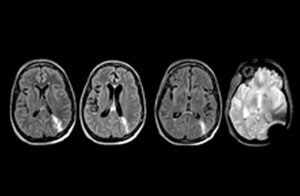

Klinische Fallbeispiele

Dieser Patient wurde mit Kopfschmerzen vorstellig, die sich bei einer Flexion des Nackens verschlimmerten, und wir sehen hier eine Chiari-Malformation vom Typ I mit niedrig liegenden Kleinhirntonsillen sowie degenerativen zervikalen, thrombolytischen Veränderungen.